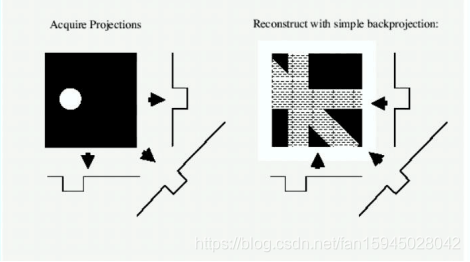

然后,根据上述已求得的信息可以建立成像模型用已知的模版进行验证对比进行调整测试,用调试好的标定模型——反投影法模型,进行数据可视化将本题给的扫描接受数据进行成像,得到数据形状等信息。

在某一断面,各点的密度值可以看成穿过该平面内该点的射线的投影值的均值,据(1)所得的标定参数,根据两种未知介质的接收情况,利用反投影重建法求出该点的密度,将每一次扫描的数据转化成矩阵进行叠加,结果即为成像图形的灰度像素矩阵。进而成像求解该介质的在正方形托盘中位置,几何形状及吸收率等相关信息,并确定图3中10个点的吸收率。

1.基本思想:断层平面成像是有灰度像素点的值大小进行的,也可以说是投影值大小决定的,该平面中某一点的密度函数值可以看作全部经过这一点的X射线的投影值的平均值。然后投影值的平均值即可当作灰度像素进行成像。

因为该CT旋转180次每次1度所以没扫描一次可其余次数得到的投影值联立起来就会构成图形信息,从而达到了图形重构的目的,成像原理如下:

图 5